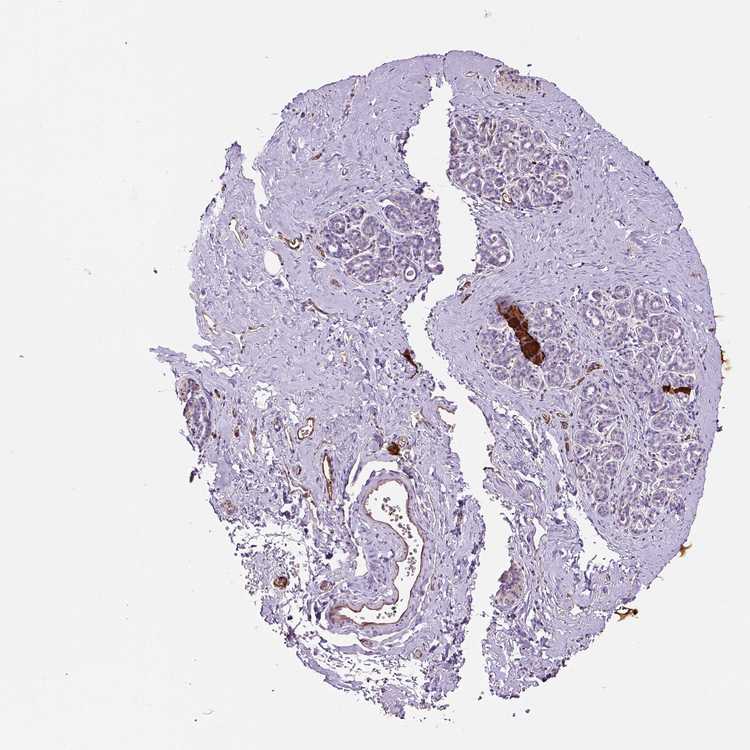

BREAST - Antibody stainingi

Antibody staining in the annotated cell types in the current human tissue is reported as not detected, low, medium, or high, based on conventional immunohistochemistry profiling in selected tissues. This score is based on the combination of the staining intensity and fraction of stained cells.

Each image is clickable and will lead to virtual microscopy that enables deeper exploration of all samples and also displays staining intensity scores, fraction scores and subcellular localization as well as patient and tissue information for each sample.

Antibody HPA001815Antibody HPA002082Antibody CAB001694Antibody CAB072874Antibody CAB072875

Adipocytes Not detectedNot detectedNot detectedNot detectedNot detected

Glandular cells Not detectedNot detectedNot detectedNot detectedNot detected

Myoepithelial cells Not detectedNot detectedNot detectedNot detectedNot detected